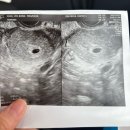

• 진해서울약국 | [서울역차병원] 시험관성공후기 (ft.김유신교수님)

안정권이라 올레를 외쳤습니다!!! ​ ​ ​ 3. 2차 피검수치 서울역차여성병원 1차 피검 후 5일뒤 임테기의 노예가 된 나.. ​ ​ 1차 피검이 안정권으로 통과다 보니 이때...정도! 물론 주사 약 질정에 따라 추가비용 발생! ​ 서류를 찾아보니 약국 질정비용은 못 찾아서 그건 포함 안된 금액입니다. ​ ​ 이건 주사 혹은 질정 처방...

산책하는 나무젓가락(2026-01-06 21:20:00)

• 진해서울약국 | 임신 4주~6주차 증상 정리 / 병원 다녀온 솔직 후기

뉴스 약국 진단 테스터기 매직아이 : 84년생 부엉이 [84년생 부엉이] 온세상을 나는 부엉이 naver.me ​ ​ 처음 해본 임테기 결과는… 👉 희미한 두 줄…? 이때 감정...아기 없어질까 봐” 불안해서 3일 뒤 또 임테기 해봄…ㅋㅋ 점점 더 진해지는 두 줄이 괜히 더 신기하고 안심되더라고요 ​ 임신 사실을 알고 그 다음주...

리미월드(2026-02-04 10:34:00)

• 진해서울약국 | 유전자 질환으로 인한 시험관 (VHL / 착상전 유전자검사 / 서울역차병원 / PGT-A, PGT-M, 이식 후기)

이식 후기를 들고 왔어요~~ ​ ​ 원래 10월 말쯤 이식을 하기로 해서 10월 중순부터 자궁내막 두껍게 만드는 약을 먹기 시작했어요! 하지만 자궁내막 얇은 이슈로 11월 5일로 이식이 미뤄졌고 이식 일주일 전부터 주사를 맞기 시작했어욥 ​ ​ 이식은 정말 5분 만에 끝난 것 같은데 이식 전 물을 500미리 먹고 참은 후 해야...

(2026-02-07 17:31:00)